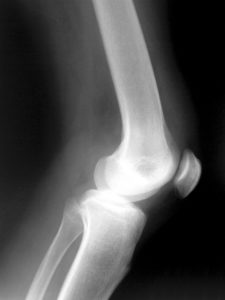

How to relieve osteoarthritis can be relieved through a physician’s care and by following an exercise regimen. Osteoarthritis in the knees can be painful for anyone who experiences it.

Those who suffer from osteoarthritis in the knees are more likely to experience difficulty walking. It can be painful to walk from one room to another, let alone leave the house.